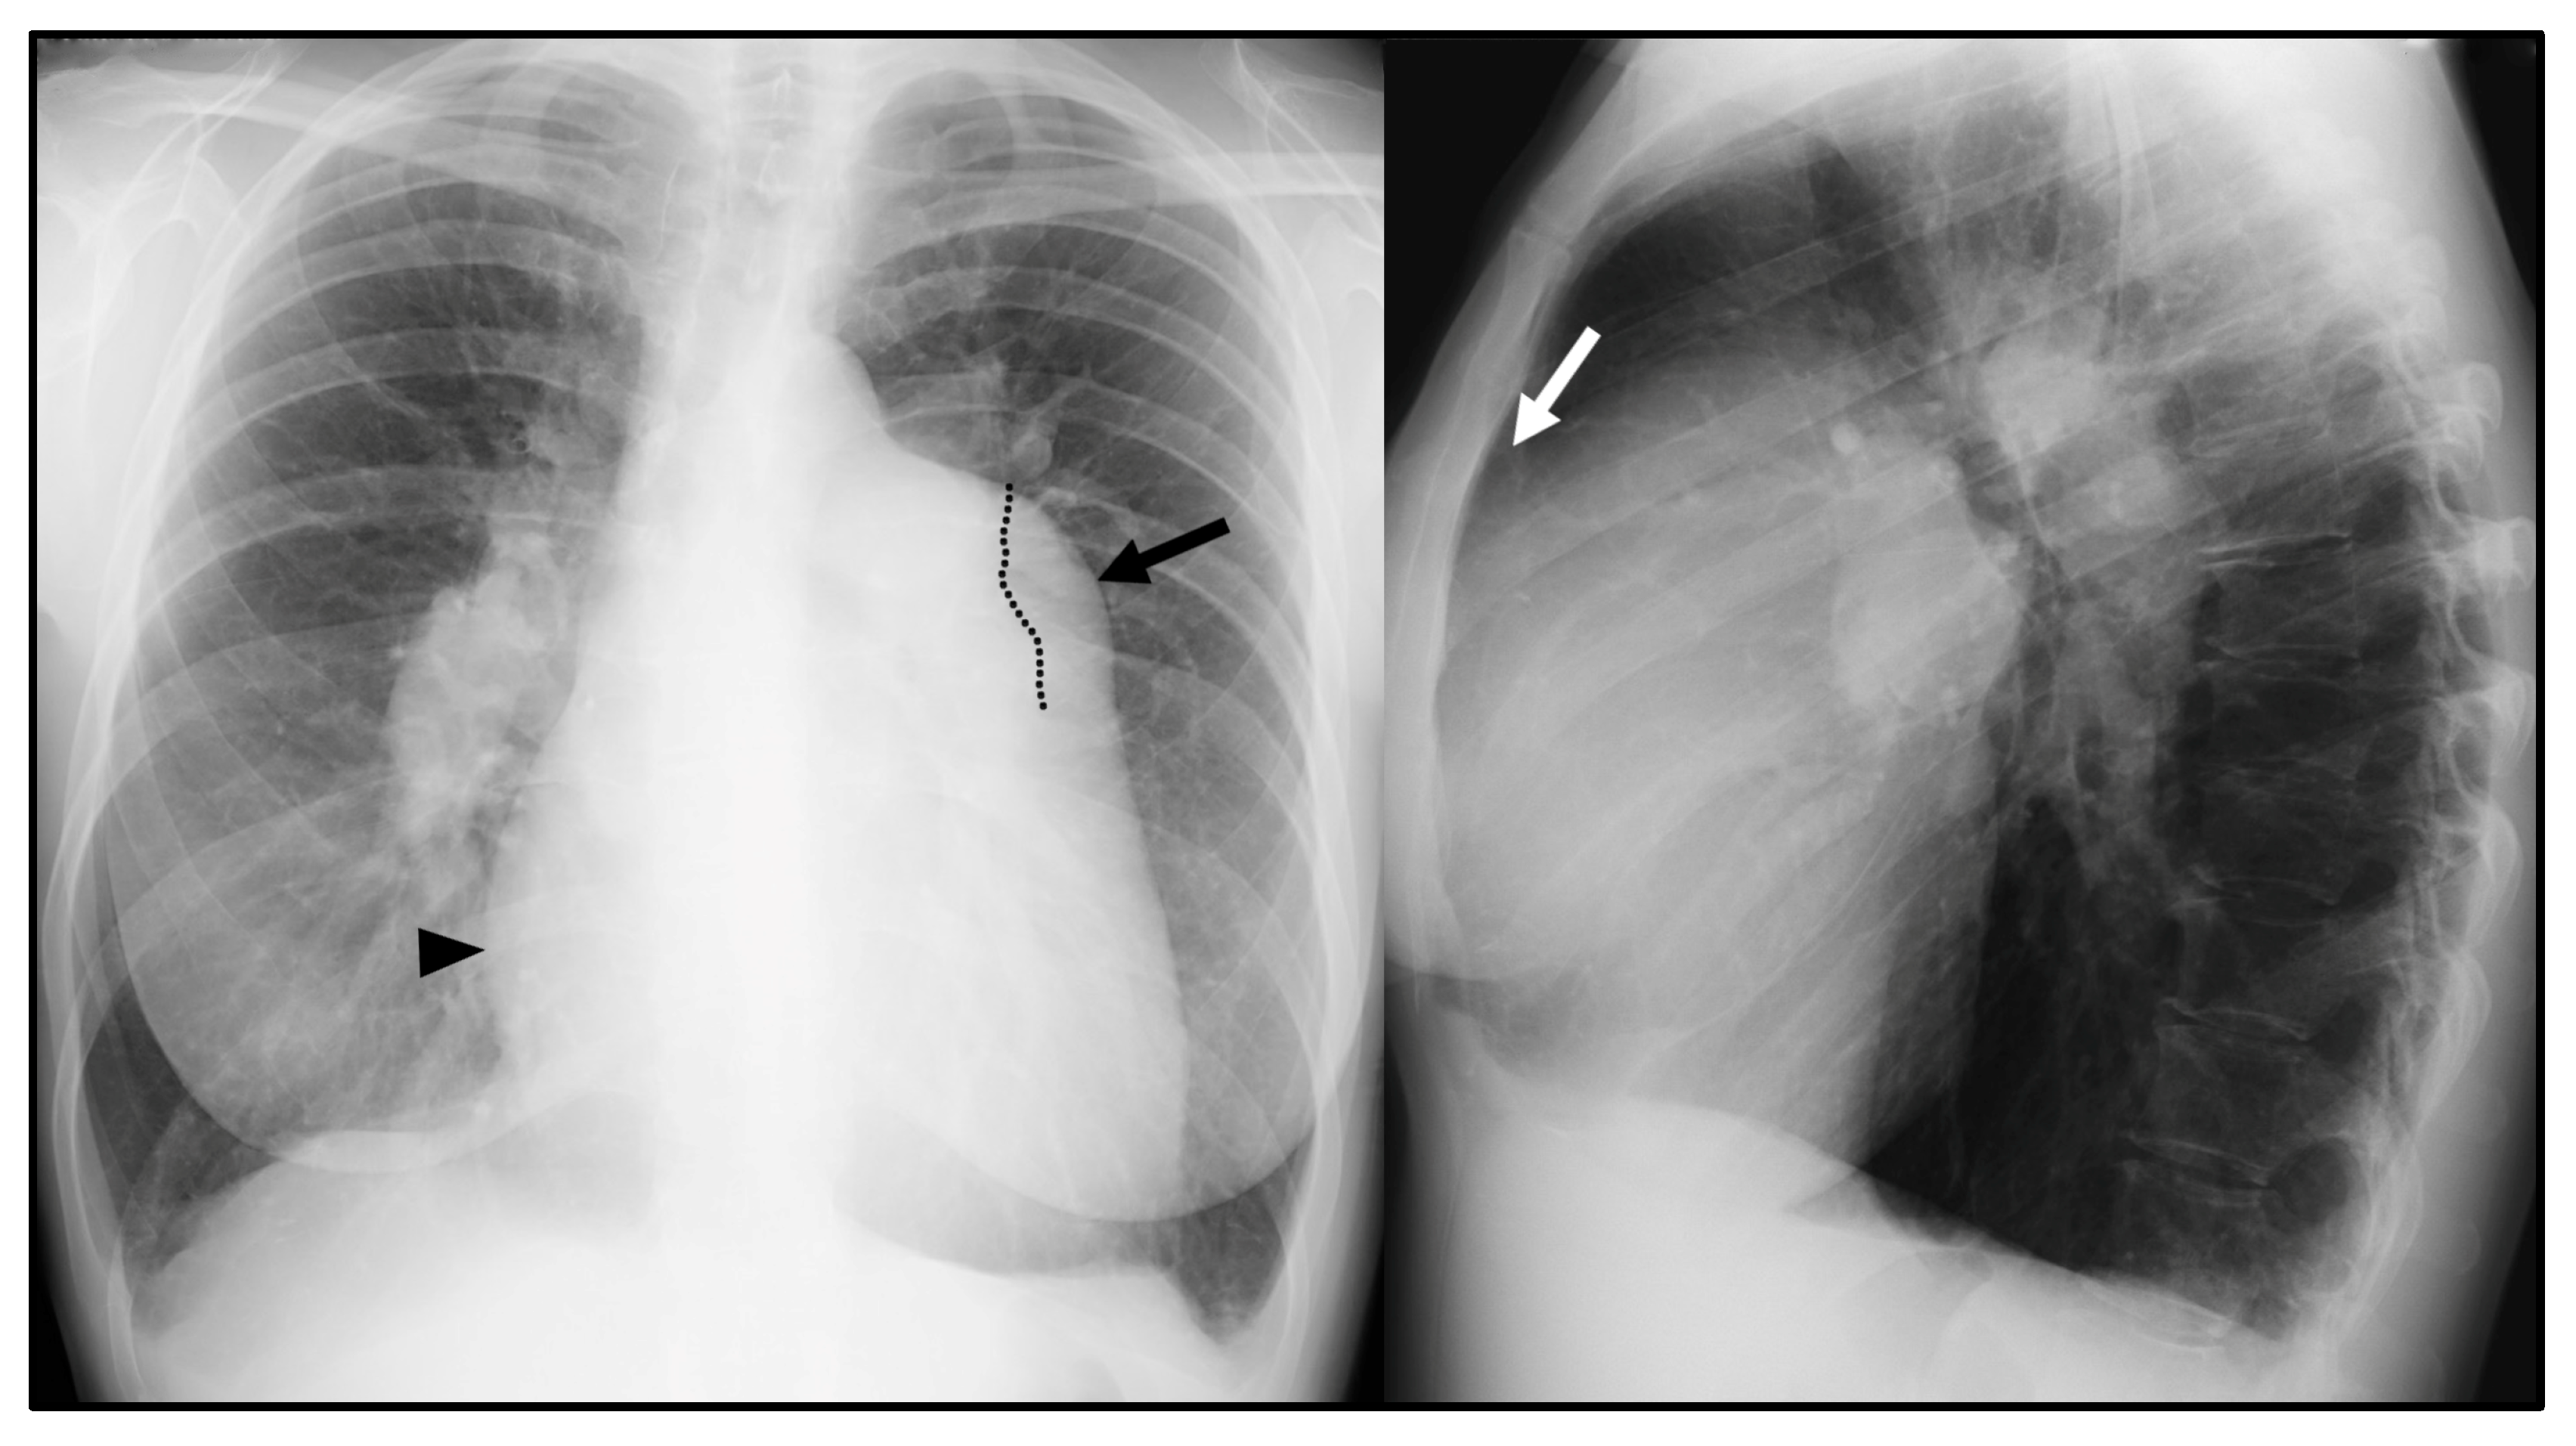

CXR is often the initial investigation in the evaluation of a patient with symptoms suggestive of PH. Even if frequently overlooked, CXR garners widespread use due to the relative ease of access, low cost [5,6], and potential capability of suggesting the presence of PH as well as the underlying cause [7]. The typical radiographic pattern of PH is characterized by the enlargement of central pulmonary arteries, associated with the tapering of the peripheral branches of pulmonary arteries, commonly referred to as pruning [7] (Figure 1). An enlarged right atrium (RA) and right ventricle (RV), commonly associated with advanced stage PH, can be evaluated on CXR as well [6]. The prominence of the right heart border (representing the RA) > 44 mm from the midline in the posteroanterior CXR and the filling of the retrosternal space in lateral film (representing RV dilation) are radiographic signs suggestive of right cardiac chamber enlargement [6]. A boot-shaped heart with an upward tilt of the cardiac apex can represent RV hypertrophy [8].

Chest X-ray (CXR) signs of pulmonary hypertension: enlarged central pulmonary arteries, with the prominence of the main pulmonary artery (MPA) (black arrow); the left pulmonary artery seen within the cardiac silhouette (dotted line); tapering of peripheral pulmonary arteries (so-called pruning); prominence of the right heart border, represented by the right atrium (black arrowhead); and filling of the retrosternal space in the lateral view due to right ventricle dilation (white arrow).